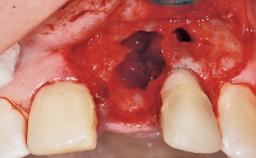

A 39-year-old male patient presented with a chief complaint of discomfort and gingival discoloration around his maxillary left central incisor. He was in good general health and was a non-smoker. His past dental history was significant because of the traumatic fracture of tooth 21 in a sporting accident at age 13. Initial dental treatment included endodontic therapy and a full-coverage restoration. The patient became symptomatic 5 years later, when structural failure of the tooth resulted in the dislodgment of the crown. Endodontic retreatment, apical surgery, and post-and-core restoration were performed.

| Bone Volume | Deficient horizontally, requiring prior grafting |

| Soft Tissue Contour and Volume | Slightly compromised |